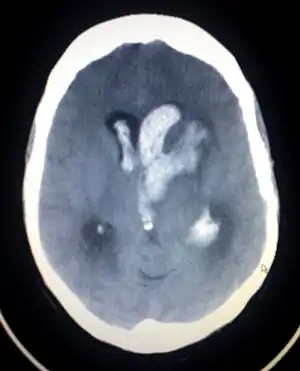

| An intracranial hemorrhage, one cause of altered level of consciousness | |

A lowered level of consciousness indicate a deficit in brain function.[4] Level of consciousness can be lowered when the brain receives insufficient oxygen (as occurs in hypoxia); insufficient blood (as occurs in shock, in children for example due to intussusception); or has an alteration in the brain's chemistry.[3] Metabolic disorders such as diabetes mellitus and uremia can alter consciousness.[12] Hypo- or hypernatremia (decreased and elevated levels of sodium, respectively) as well as dehydration can also produce an altered LOC.[13] A pH outside of the range the brain can tolerate will also alter LOC.[9] Exposure to drugs (e.g. alcohol) or toxins may also lower LOC,[3] as may a core temperature that is too high or too low (hyperthermia or hypothermia). Increases in intracranial pressure (the pressure within the skull) can also cause altered LOC. It can result from traumatic brain injury such as concussion.[12] Stroke and intracranial hemorrhage are other causes.[12] Infections of the central nervous system may also be associated with decreased LOC; for example, an altered LOC is the most common symptom of encephalitis.[14] Neoplasms within the intracranial cavity can also affect consciousness,[12] as can epilepsy and post-seizure states.[9] A decreased LOC can also result from a combination of factors.[12] A concussion, which is a mild traumatic brain injury (MTBI) may result in decreased LOC.